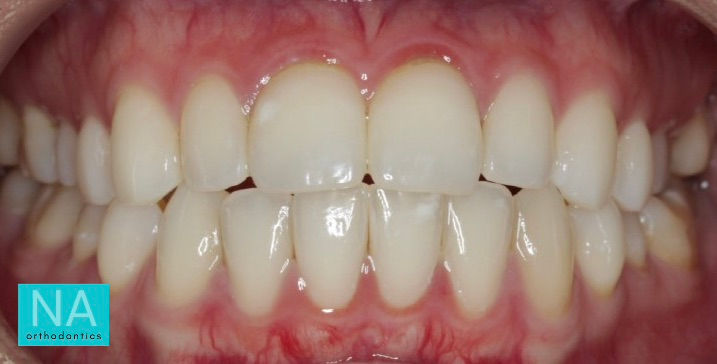

Patient After Invisalign

After Invisalign at NA Orthodontics, open bite is closed, flaring and protrusion are reduced, ideal overbite and overjet achieved.